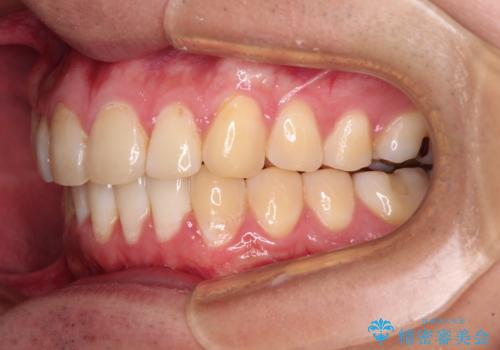

- 上下前歯のデコボコを気にして来院された患者様です。

前歯のデコボコ以外に左側の奥歯の咬み合わせに問題がありましたが、価格を抑え、短期間で気になる前歯を治したいとのことでした。

写真より左側臼歯の咬合がタイトではないことが分かりますが、こちらは保定期間に徐々に咬合させていくこととしました。